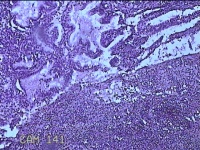

宫颈管组织

性别

女

年龄

33岁

临床诊断

异位妊娠

一般病史

停经52天,阴道流血12天。

标本名称

大体所见

灰白暗红色不规则碎组织4.3x3.3x1.2cm一堆。

图1